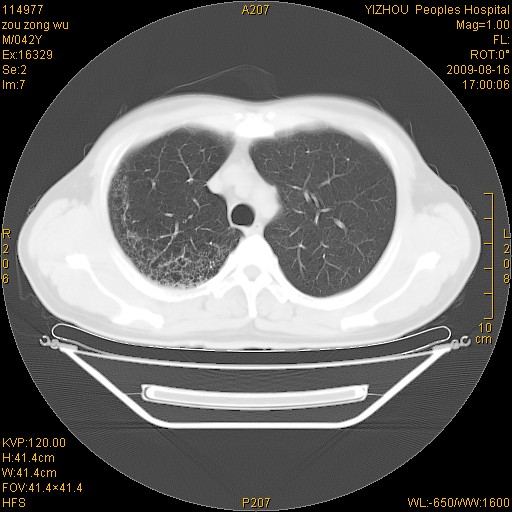

以下是引用zjzjr在2009-8-17 10:42:00的发言:[br]右侧间质性肺炎伴纤维化,右肺下叶肺囊肿伴感染(不除外外伤后引起),右肺野及胸壁软组织\\肝内见多发斑点状,中枪了吧.右侧胸膜肥厚\\粘连.